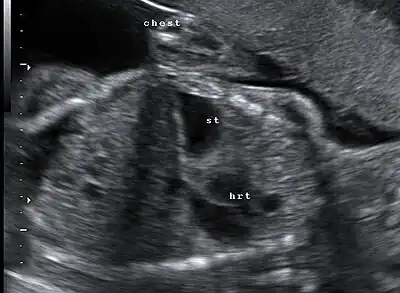

Congenital diaphragmatic hernia: coronal obstetric ultrasound (head to right of image, thorax centre, abdomen left) shows the stomach and heart both within the thorax.